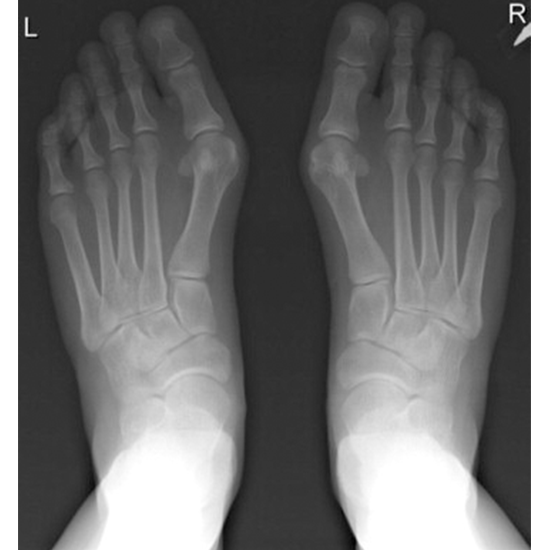

The Anteroposterior (AP) View of Both Feet is used to see the bones of the feet, such as the ankle bones (tarsal bones), the front of the feet (metatarsal bones), the toes (phalanges), and the soft tissues (skin and muscles) around them.

• To find out if any bones in the feet are broken or fractured and to watch how the broken bone heals after it has been set.

• To find out if you have an infection, osteoporosis, bone deformities, or abnormal bone growth (inflammation of the joints).